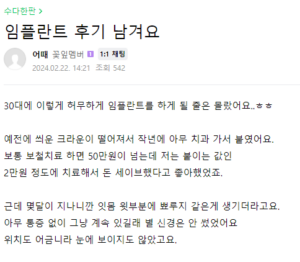

어금니 임플란트 실제 후기

위는 실제 어금니 임플란트에 대한 후기입니다. 처음에 할 때에는 두려움이 있을 수 있지만, 역시나 많은 사람들이 만족해하는 것을 볼 수 있습니다. 다만 엄연히 수술이기 때문에 어느정도의 회복기간인 필요한 점 참고해주세요.